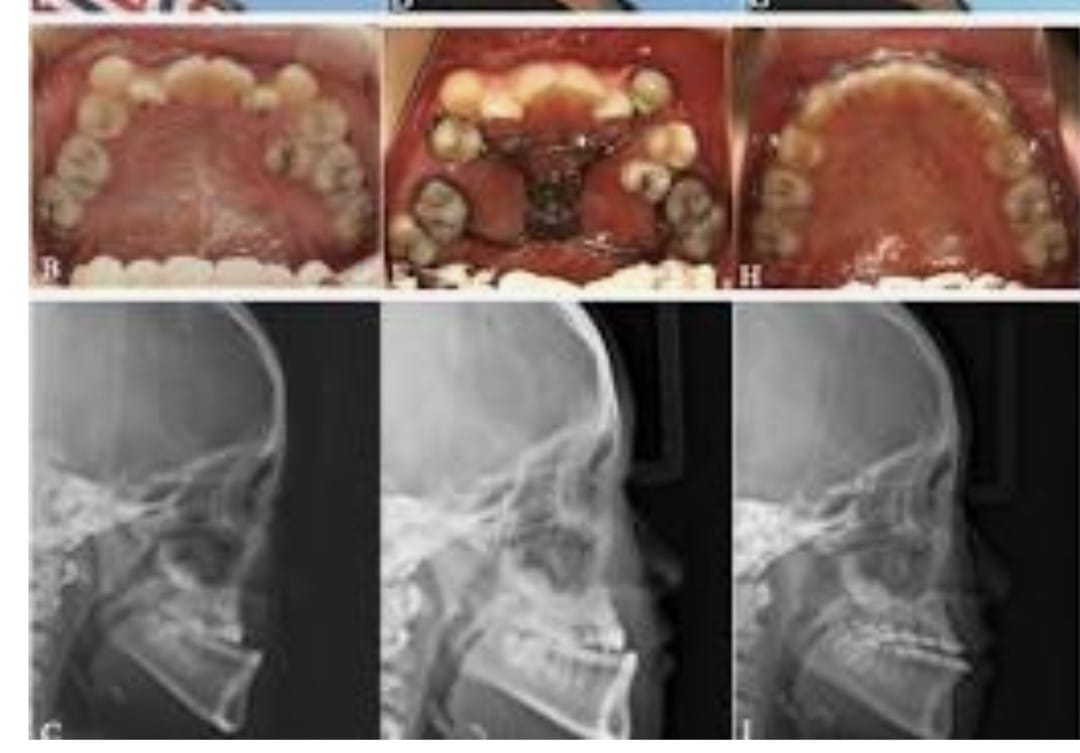

A deficient mandible refers to an underdeveloped or retruded lower jaw that can affect the balance and harmony of the facial profile. This condition may be present from birth or may develop due to growth abnormalities, trauma, or certain medical conditions. A recessed lower jaw can lead to functional concerns such as difficulty in chewing, speech issues, or improper bite alignment, in addition to affecting facial aesthetics.

Treatment for a deficient mandible focuses on restoring proper jaw position and improving overall facial balance. Depending on the severity, procedures may include jaw advancement surgery or other corrective surgical techniques designed to reposition and enhance the structure of the lower jaw. With careful evaluation and modern surgical methods, treatment helps improve both facial appearance and functional outcomes, providing long-term stability and enhanced confidence.

- Pre-surgical Orthodontics: Often needed before the actual surgery takes place. Imaging: X-rays and CT scans are required.